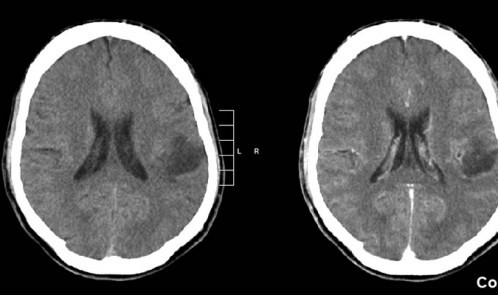

021E6912000004B0-3054495-image-a-21_1429907907705

با انجام این آزمایش، مراحل رشد تومور در گلیوم پیشرفته کاملا مشخص شده است و محققان به دنبال روشی برای درمان هستند. آنان بر این باورند که با مسدودکردن مسیرهای شیمیایی که تومور برای رشد به آنان وابسته است، می توان فعالیت سلول های تومور مغزی را محدود کرد، زیرا نمی توان از مریض درخواست کرد که فکر نکند.